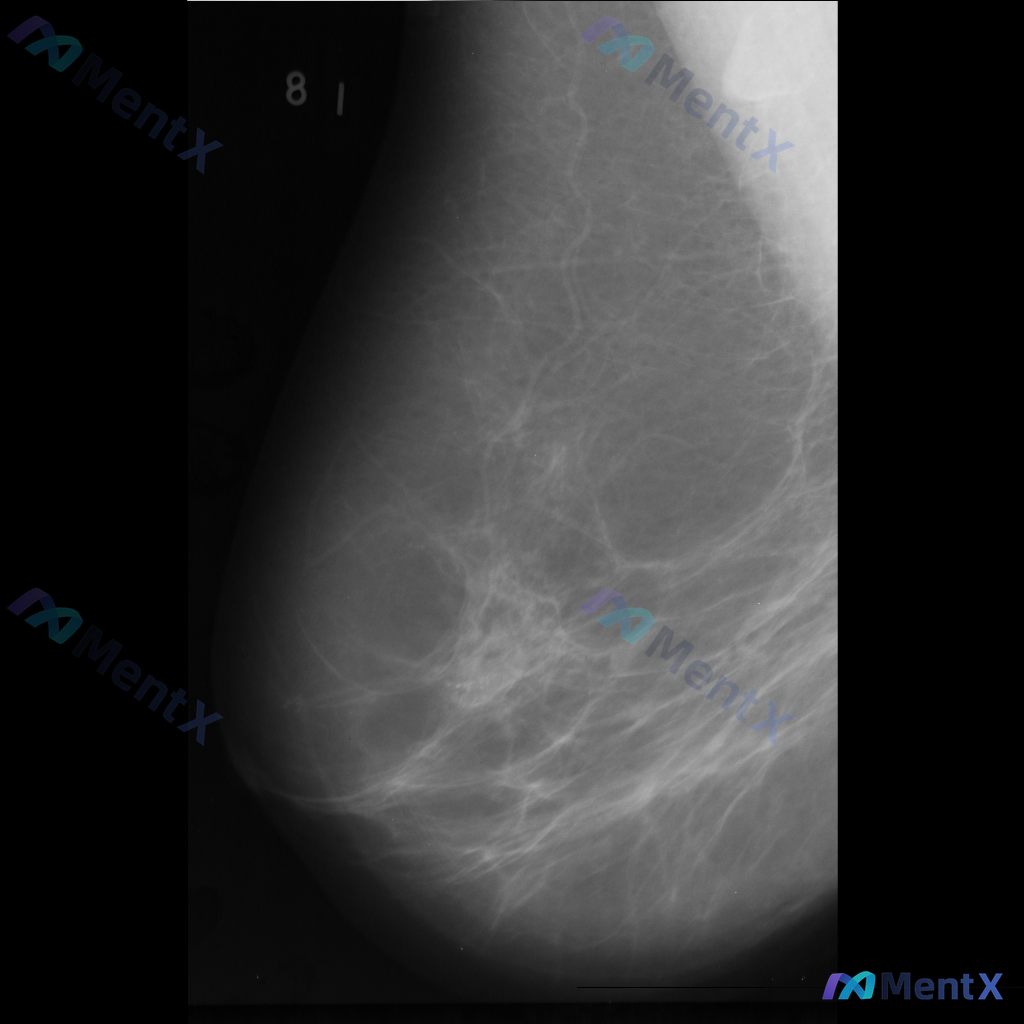

这张乳腺钼靶影像的异常表现,你会优先考虑哪种情况?

整理到一份乳腺钼靶影像资料,主要异常表现如下:

- 部位:乳腺中部偏下方

- 影像征象:局灶性不规则腺体密度增高,伴结构扭曲

- 背景:致密型乳腺

目前仅单张影像资料,未提供其他体位、超声或临床病史。

想和大家讨论一下:单看这组异常表现,你会先往哪个方向考虑?后续如果要进一步明确,你觉得优先做什么检查?